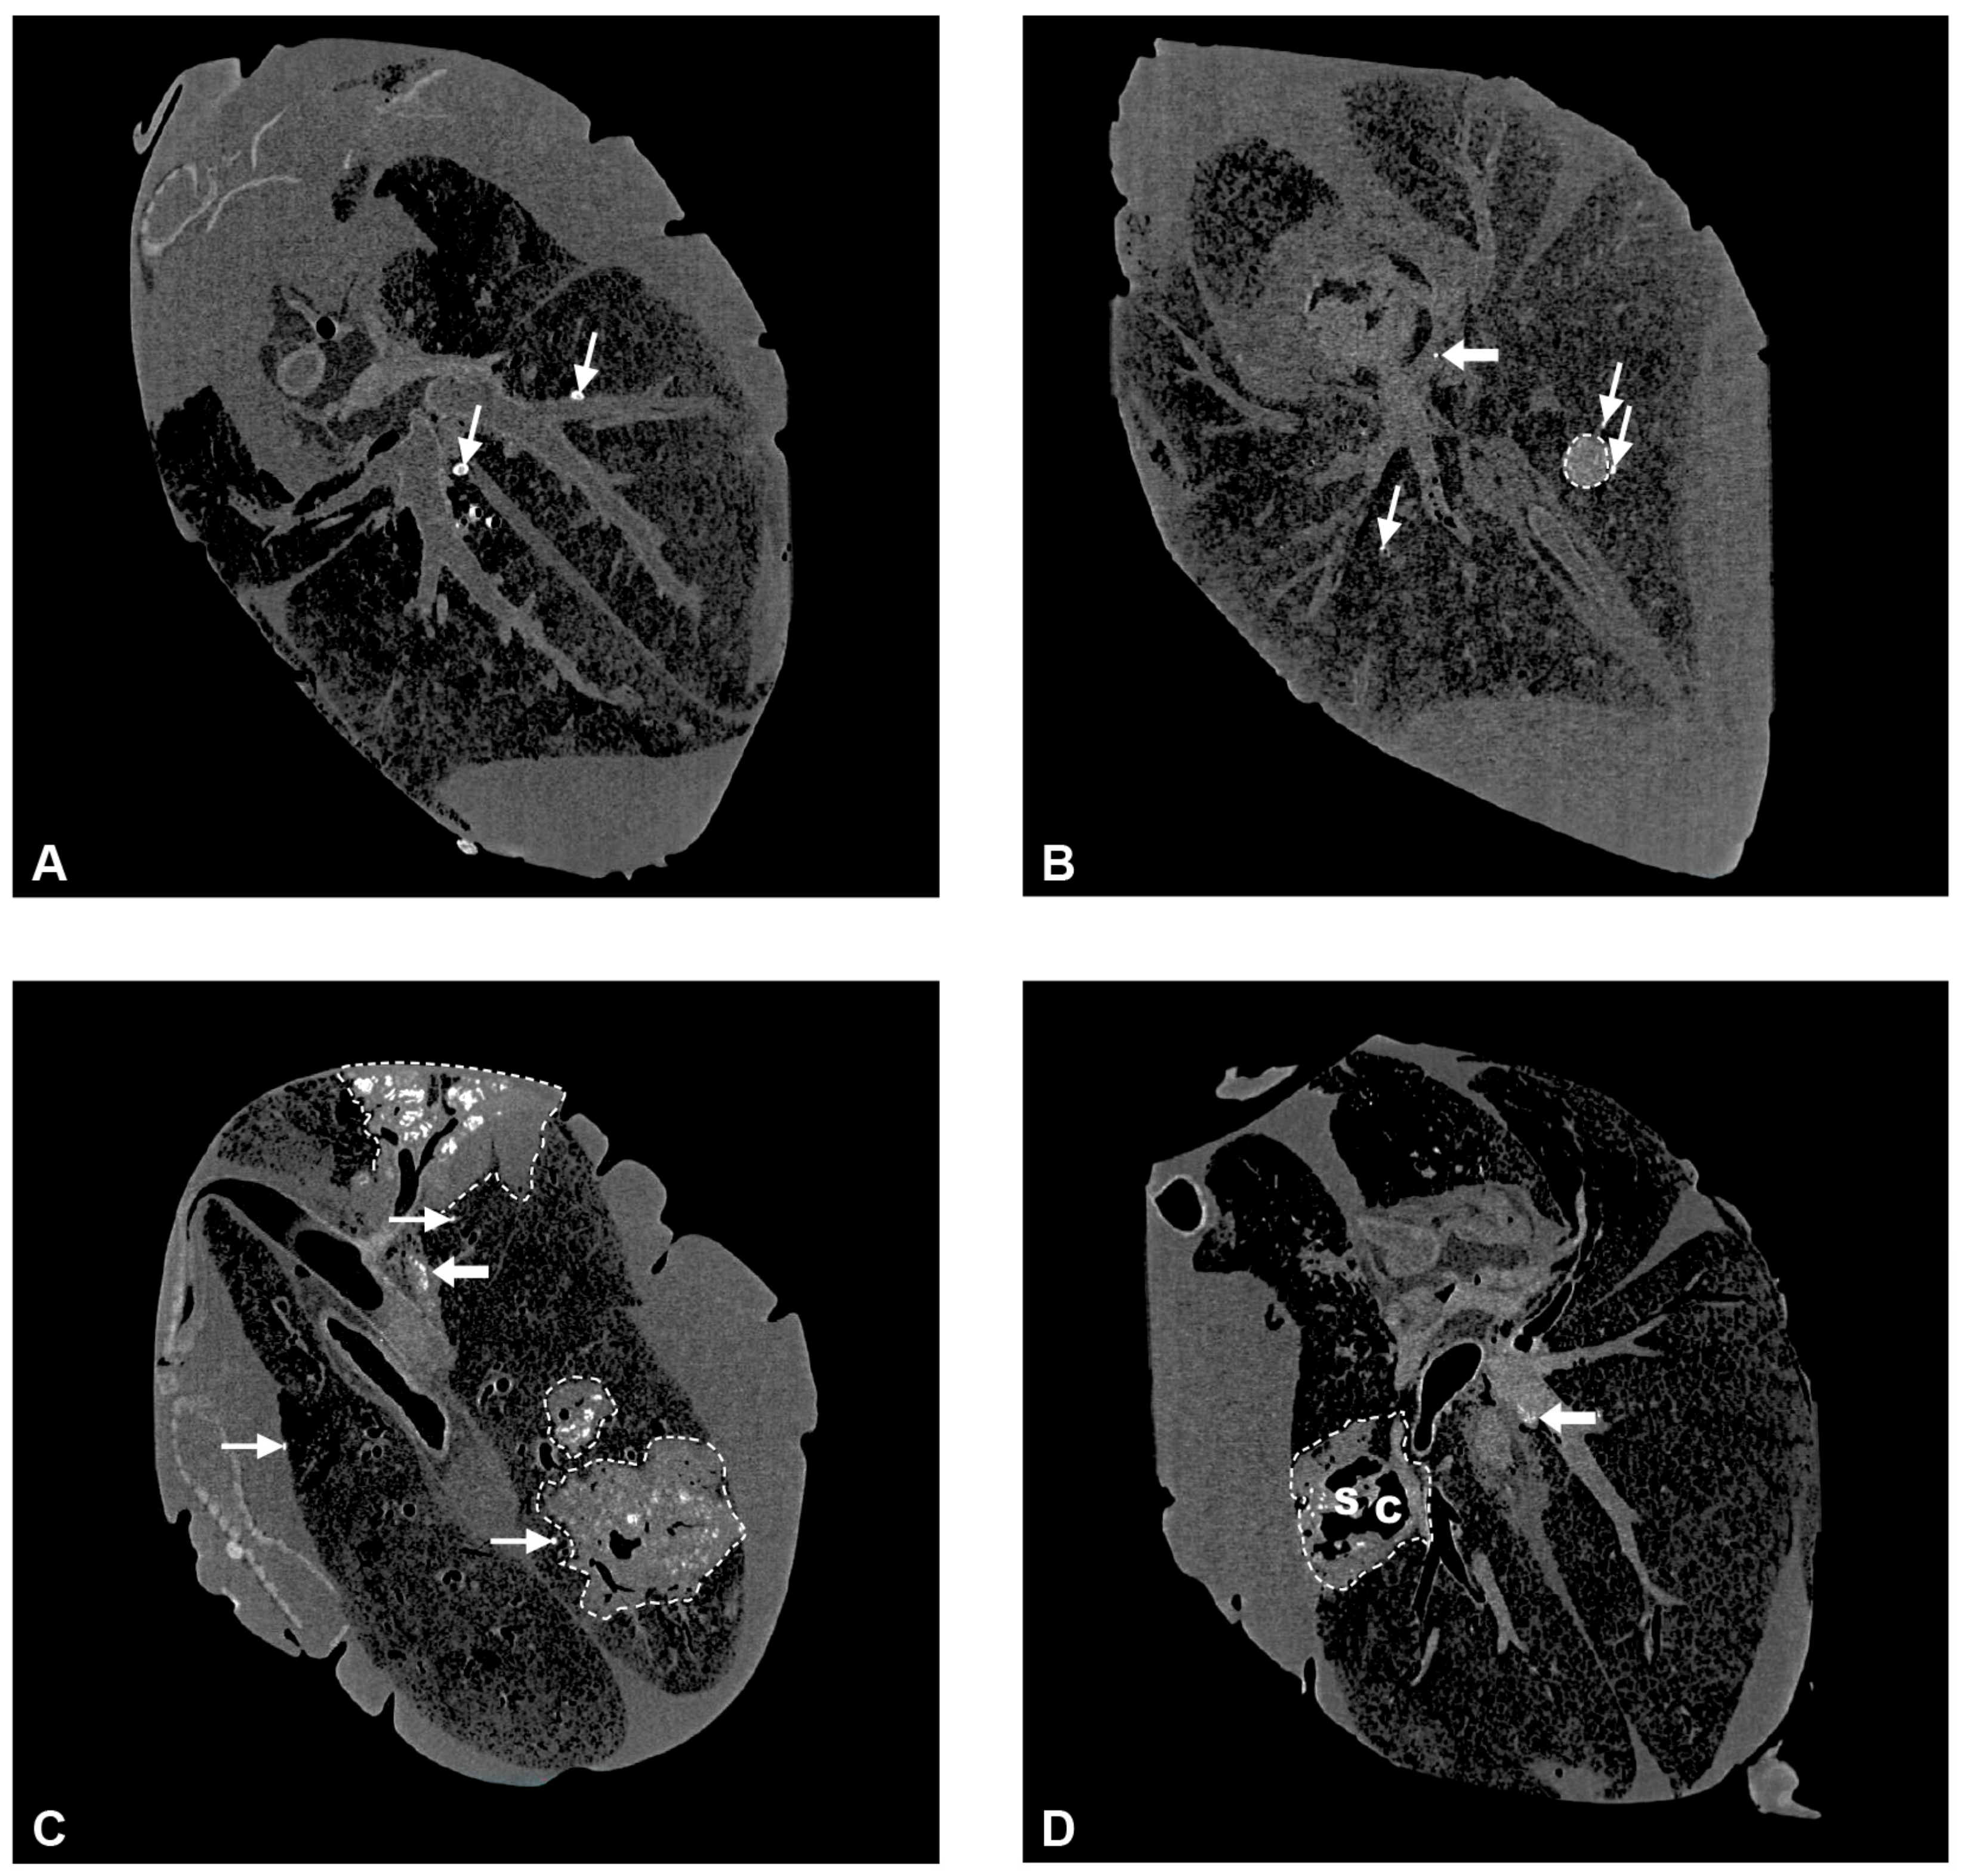

2.5. Computed Tomography Imaging (CT) of Lungs from M. bovis-Inoculated Goats

- Wedlich, N.; Figl, J.; Liebler-Tenorio, E.M.; Köhler, H.; von Pückler, K.; Rissmann, M.; Petow, S.; Barth, S.A.; Reinhold, P.; Ulrich, R.; et al. Video endoscopy-guided intrabronchial spray inoculation of Mycobacterium bovis in goats and comparative assessment of lung lesions with various imaging methods. Front. Vet. Sci. 2022, 9, 877322. [Google Scholar] [CrossRef]